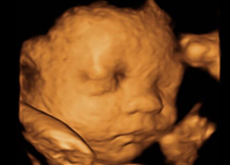

四維彩超它是目前最先進(jìn)的彩超設(shè)備,說(shuō)起四維彩超的功能和作用,相信只要是懷孕過(guò)的媽媽們一定都十分清楚,四維彩超不僅可以檢測(cè)篩查胎兒畸形,而且它還可以很全面的檢測(cè)出寶...